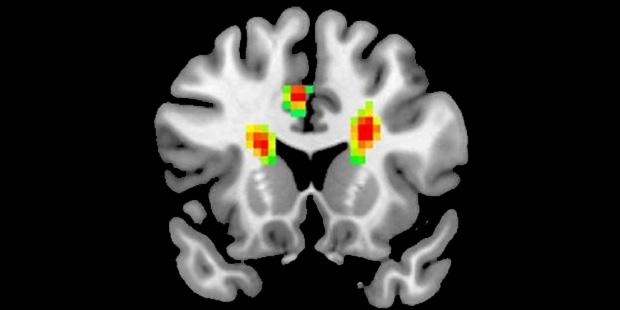

Araştırma sonucuna göre, aşıkken beynimize giden kan miktarı artıyor ve beynimizin 12 bölgesi aktif oluyor. Beynin önde gelen fonksiyonel değişiklikleriyle ilgili ilk amfirik kanıtını gözler önüne seren araştırma, aşkın insanlar üzerindeki etkilerini tam olarak açıklığa kavuşturmasa da işe bir yerlerden başlıyor.

MR görüntülerine göre aşık olduğumuzda korku kontrolü, muhakeme, negatif duyguları kontrol etme ve empati gibi yeteneklerimizi geçici olarak kaybediyoruz. Beyin dalgaları üzerinde yapılan araştırmaya göre tutkunu olduğumuz birine baktığımızda değerlendirme yapabilme yeteneğimizi geçici olarak kaybediyoruz.